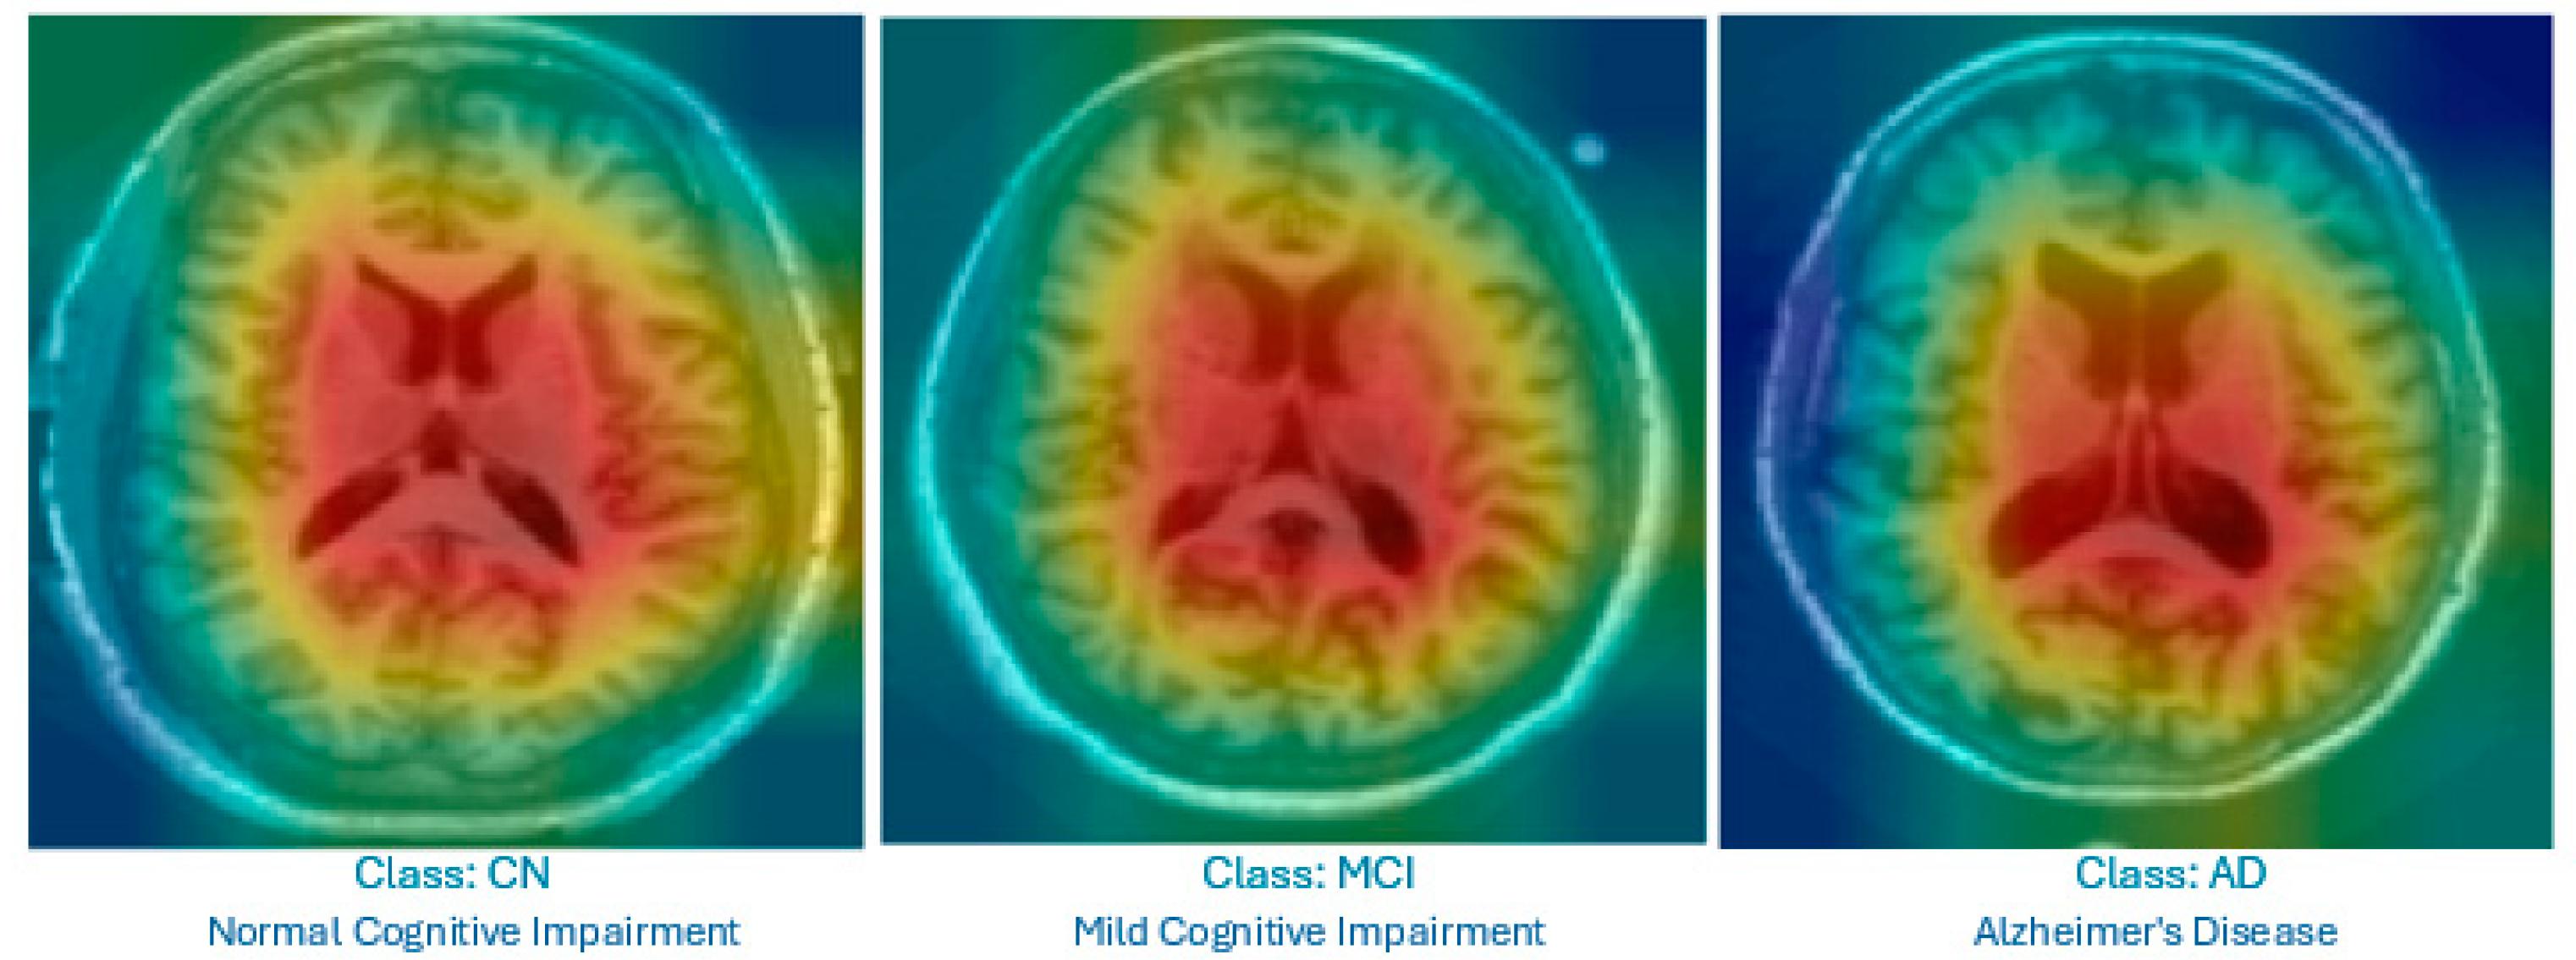

- Grad-CAM is used for MRI images. It produces heat maps superimposed on the original slices to highlight the brain regions that influenced the classification, helping non-radiologists visualize relevant anatomical patterns.

- Focusing on specific MRI slices to enhance explainability: Our model restricts analysis to middle slices that show the lateral ventricles, which are well-known indicators of AD-related atrophy. This strategy enhances the explainability and clinical relevance of the visual output.